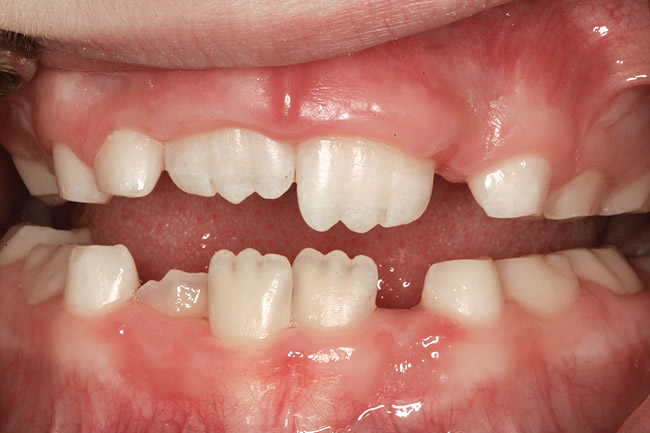

(10.) Narrow maxilla with tooth wear and bilateral crossbite.

Figure 10

The point of obstruction tends to determine the type of skeletal impact. Nasal obstruction from enlarged turbinates, blocked ostium maxillare, deviated septum, or nasal valve stenosis creates Angle occlusions of Class I, II, and III equally (Figure 8). The maxilla in these cases is positioned posteriorly and the mandible is posterior-inferior. The facial type is most commonly dolicocephalic. Blockage of the airway predominately by the adenoids will create growth patterns that yield mostly Class II occlusions and anterior open bite with both jaws located posterior-inferiorly. Facial type is again dolicocephalic with the typical long-thin “adenoidal” face49 (Figure 9 through Figure 12). If the tonsillar tissue is responsible for the airway obstruction, the tongue will have an abnormal resting posture. Class III occlusions will be more common with the maxilla normal or posterior placed (Figure 13 through 15). The tongue may direct the mandible anteriorly or, because the tongue is not in the roof of the mouth driving A point anterior, the maxilla will become bimaxillary retrusive.50 In some cases, the anterior posture of the tongue will create an open bite. This is incorrectly referred to as a tongue thrust. The impact from a thrust does not alter the tooth position. Long-term, low forces cause tooth movement. The posture of the tongue against or between the anterior teeth due to the excessive tonsillar size creates the open bite (Figure 16 and Figure 17). Facial types in this group are more brachyfacial. Lastly, if the airway is blocked through a combination of factors, the Angle classification will be either Class II or III. The maxilla will be in a normal location and the mandible will be the affected arch (Figure 18). These craniofacial changes are not restricted to OSA; all SDB will create unique alterations depending on the patient compensation. Children with UARS have been reported to display high, narrow palates, dolicofacial form, and a Class II malocclusion, indicative of largely adenoidal blockage.51

In some children, T&A alone may not completely resolve the OSA (Figure 19 and Figure 20). The longer the airway dysfunction, the greater the structural impact on the airway. An interdisciplinary clinical study54 was conducted on children approximately 6.5 years old with inclusion criteria of OSA, large tonsils, visually constricted airway, and high and narrow palate. Group 1 was treated with rapid maxillary expansion (RME) and Group 2 with T&A. Maxillary expansion has been shown to create improved nasal resistance and an increase nasal cavity volume. In cases without excessive lymphoid hypertrophy, RME can resolve significant levels of OSA.55,56 After the original therapy, only one child had been completely resolved (apnea-hypopnea index [AHI] <1). The remaining subjects switched groups and received the opposite treatment. After receiving both treatments, 29 of the 31 children were cured. It can be concluded that many children must be treated with multiple therapies before resolution, especially if the SDB has previously altered the airway to a significant degree.